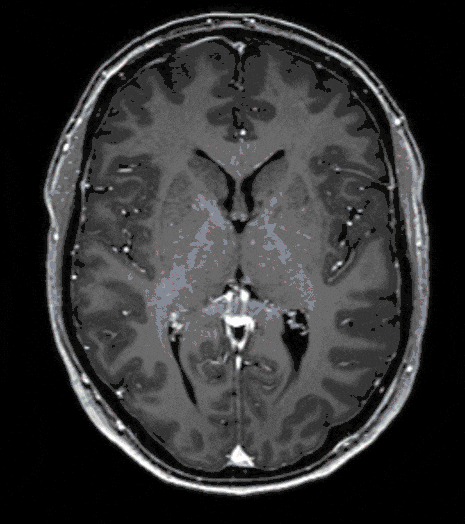

Glioblastoma

Glioblastomas are among the most aggressive tumors of the brain and usually develop directly from healthy cells but can also arise secondarily from benign precancerous lesions (see Gliomas).